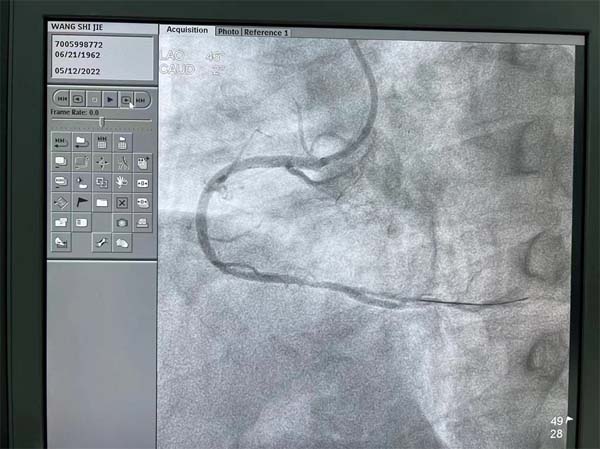

应急总医院心血管内科的疾病经常是突如其来,来势汹涌。一位59岁的男性患者在常规冠脉CT检查中发现右冠状动脉(RCA)有严重的狭窄,同时合并有十二指肠球部溃疡,患者平时没有严重的胸闷胸痛等症状,入院心电图和超声心动图检查也都正常,患者本人对检查结果还有一些意外。吴迪副院长查看该病人冠脉CT后给予了准确判断,患者RCA是完全闭塞(CTO)病变,术前一天根据患者情况制定了术中抗凝抗栓方案,患者进入导管室后实施冠脉造影,果然不出所料:RCA在近端完全闭塞,左冠脉向RCA提供部分侧支循环,RCA闭塞处有部分前向桥侧支,闭塞段超过2cm。闭塞段有部分钙化,远端血管可供登录部分比较细,增加了开通困难。吴迪副院长仔细研判造影图像,并结合冠脉CT图像,评估患者RCA闭塞血管的走形,并充分与患者本人及家属沟通,详细告知病情。

CTO病变目前还是冠脉介入治疗的难点,即便最有经验的冠脉介入医生,成功开通CTO病变的成功率也只有80-90%。吴迪副院长审时度势,迎难而上,制定前向开通方案,选择了强支撑的指引导管,在Sion导丝和微导管送至RCA闭塞处近段,逐步升级导丝,精确操控导丝,终于在微导管支撑下,多次突破闭塞处坚硬病变后,Gaia2导丝顺利到达RCA远段真腔,把微导管送至RCA远段后交换成工作导丝,从小球囊到大球囊,逐渐将闭塞病变充分预处理后置入两枚支架,RCA成功再次恢复通畅,血流恢复正常TIMI3级。手术在最短时间结束,患者平稳转至CCU监护病房,患者和家属一直悬着的心终于放了下来。患者激动地说:“心内科团队把80-90%可能变成了100%成功,太棒了!”